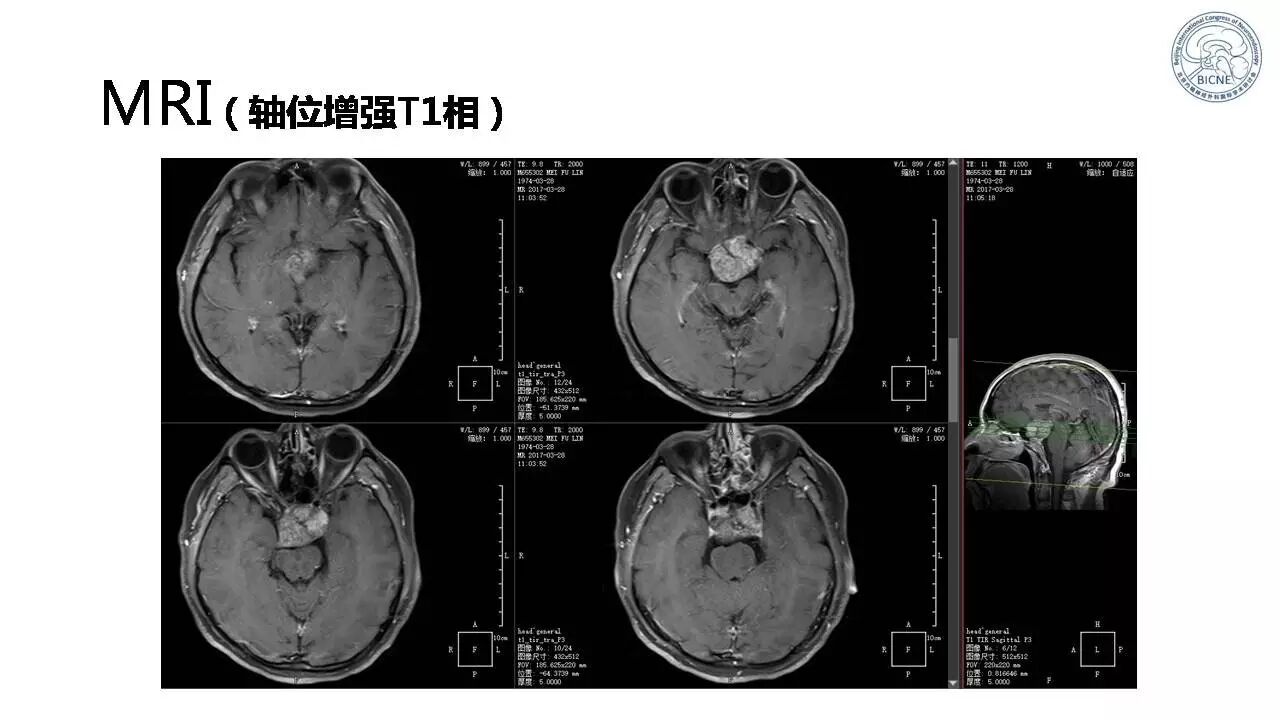

(一)张亚卓教授:脊索瘤经鼻内镜下治疗